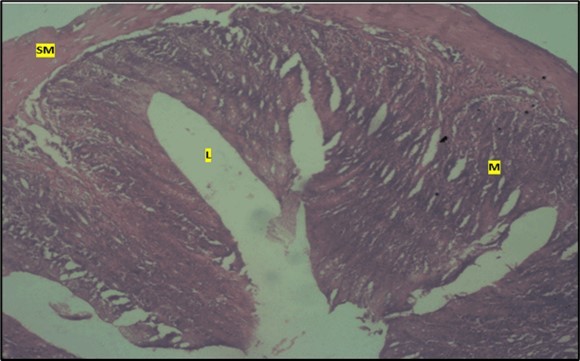

Micrographs of The Small Intestine

Histological examination of the small intestine result in control animals revealed a normal architecture with the red pulp and white pulp with no pathological observation Figure 2. Administration of Abelmoschus esculentus at low dose shows an increased cellularity with numerous cells in the Mucosa and the villi projecting towards the lumen. Focal metaplasia of mucosal cells alongside villous disruption was also observed (Figure 3). The high dose group showed normal cellular architecture with no villous disruption (Figure 4).

Figure 2.Control showing the mucosa with intestinal villi (v) projecting towards the lumen (l) and the underlying smooth muscle layer (sm) all appearing normal

Figure 3.Low dose showing numerous epithelial cells in the mucosa (m) with villi projecting towards the lumen (l). The is focal metaplasia of the mucosal cells with villous disruption. smooth muscle layer appears normal. H & E. X40

Figure 4.High dose showing a normal mucosa (m) with villi (v) projecting towards the lumen(l) and underlying smooth muscle layer (sm). No pathology seen